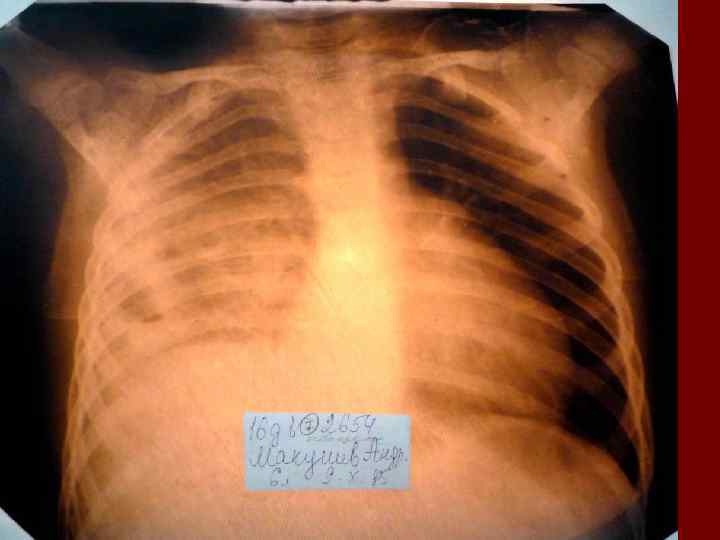

Пневмония Воспалительный процесс в респираторных отделах легкого с наличием внутриальвеолярной экссудации. n Это острое инфекционное заболевание легочной паренхимы, диагностируемое по синдрому дыхательных расстройств и/или физикальным данным при наличии очаговых или инфильтративных изменений на рентгенограмме. n Пневмония – это, прежде всего, клинический диагноз, который ставит врач у постели больного, и только затем подтверждает рентгенологически. n

Пневмония - это неспецифическое воспаление легочной ткани, в основе которого лежат инфекционный токсикоз, дыхательная недостаточность, водно – электролитные и прочие метаболические нарушение с патологическими изменениями во всех органах и системах детского организма. Заболевание диагностируется на основании синдрома дыхательных расстройств и/или физикальных данных и верифицируется рентгенологически выявлением инфильтративных изменений в легких.

Показания к назначению рентгенологического исследования: - лихорадка в течение 3 и более дней при наличии кашля; - одышка; - цианоз; - выраженные симптомы интоксикации; - типичные аускультативные или перкуторные изменения ( особенно асимметричной локализации).

Морфологическую форму пневмонии определяют по клинико – рентгенологическим данным: выделяют очаговую, очагово – сливную, долевую ( крупозную), сегментарную и интерстициальную пневмонии. Очаговая – наиболее распространенная форма. Пневмонические очаги чаще бывают размером 1 см и более. Очагово – сливная – инфильтративные изменения в нескольких сегментах или во всей доле легкого, на фоне которых могут быть видны более плотные участки инфильтрации и/или полости деструкции. Сегментарная – в процесс вовлекается весь сегмент, который, как правило, находится в состоянии гиповентиляции, ателектаза. Морфологическая картина воспаления при очаговых и сегментарных пневмониях связана с первичным инфекционным воспалением в бронхах, что дает основание отнести эти варианты поражения легочной ткани к бронхопневмониям, нередко сопровождающихся бронхообструктивным или бронхообтурационным синдромами. В настоящее время данный тип пневмоний у детей встречается наиболее часто.